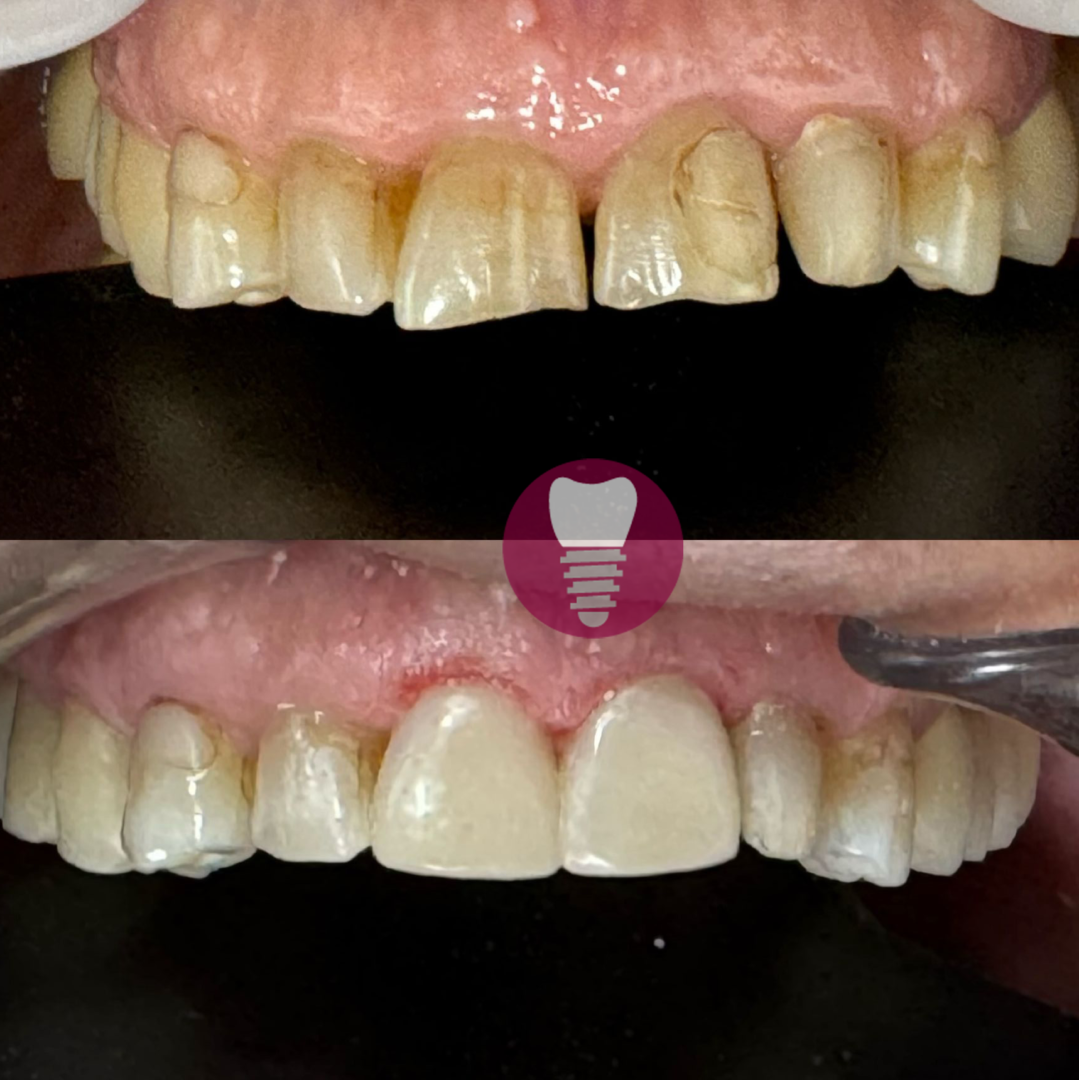

Las carillas dentales son láminas finas de material cerámico o resina compuesta que se adhieren a la superficie de los dientes para mejorar su apariencia. Este tratamiento es ideal para corregir imperfecciones como manchas, fracturas, microdoncia o caries visibles, devolviendo a los dientes un aspecto estético y natural. Las carillas se diseñan a medida, adaptándose al tamaño, color y forma de cada diente para lograr un resultado armonioso y duradero.

1.4 – Carilla de alta estética dental por caries